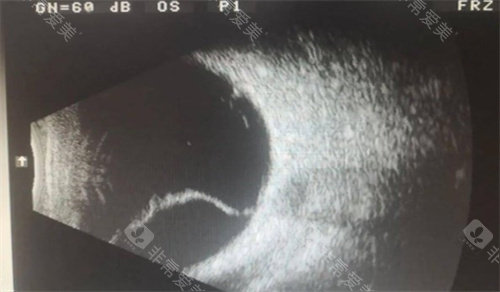

欧科路视野仪、日本拓普康非接触眼压计、电生理检查仪、眼底荧光造影仪等设备,为眼科疾病的诊断提供了多方面、更准的依据,能帮助医生更及时、更准地发现患者的眼部问题。